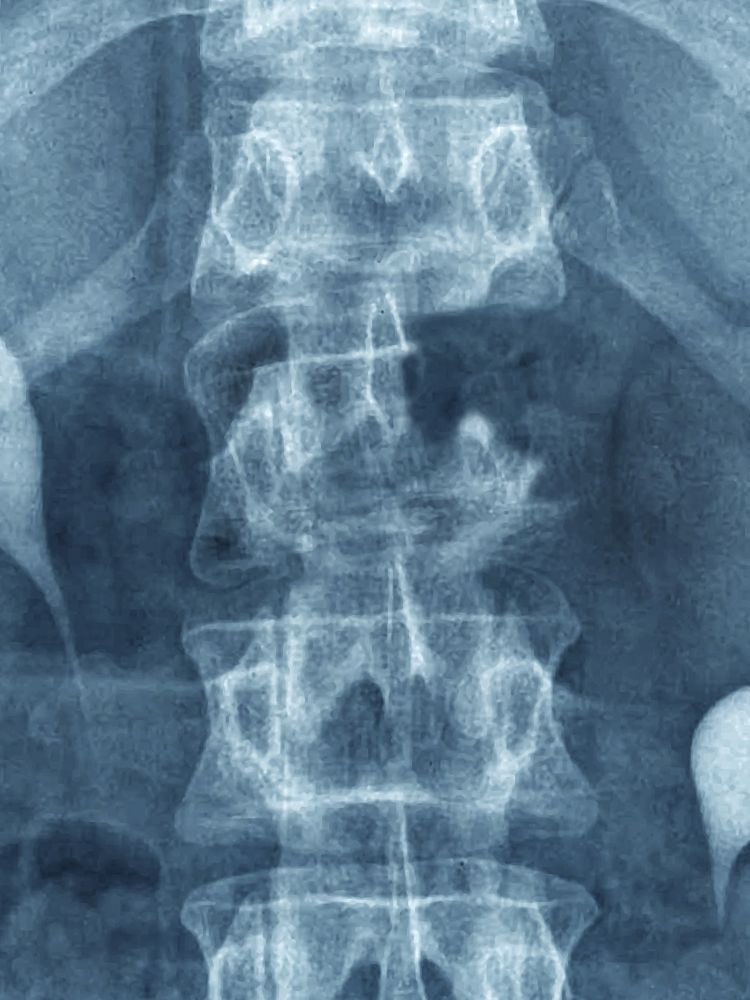

Рентген шейных позвонков при спина бифида

Раздел: Фотозарисовки